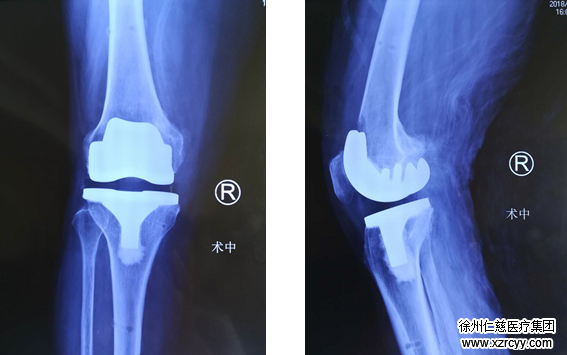

(术后计算机导航辅助精准测量:内翻1°,屈曲1°)

6月20日,在betway在线登陆关节外科团队的努力下,李奶奶的手术顺利完成,从上图计算机导航捕捉数据来看,力线误差仅1°,非常精确。术后第三天,李奶奶便下床进行恢复性锻炼,4来年的第一次自由行走,让她激动不已。

(置换后检查资料)